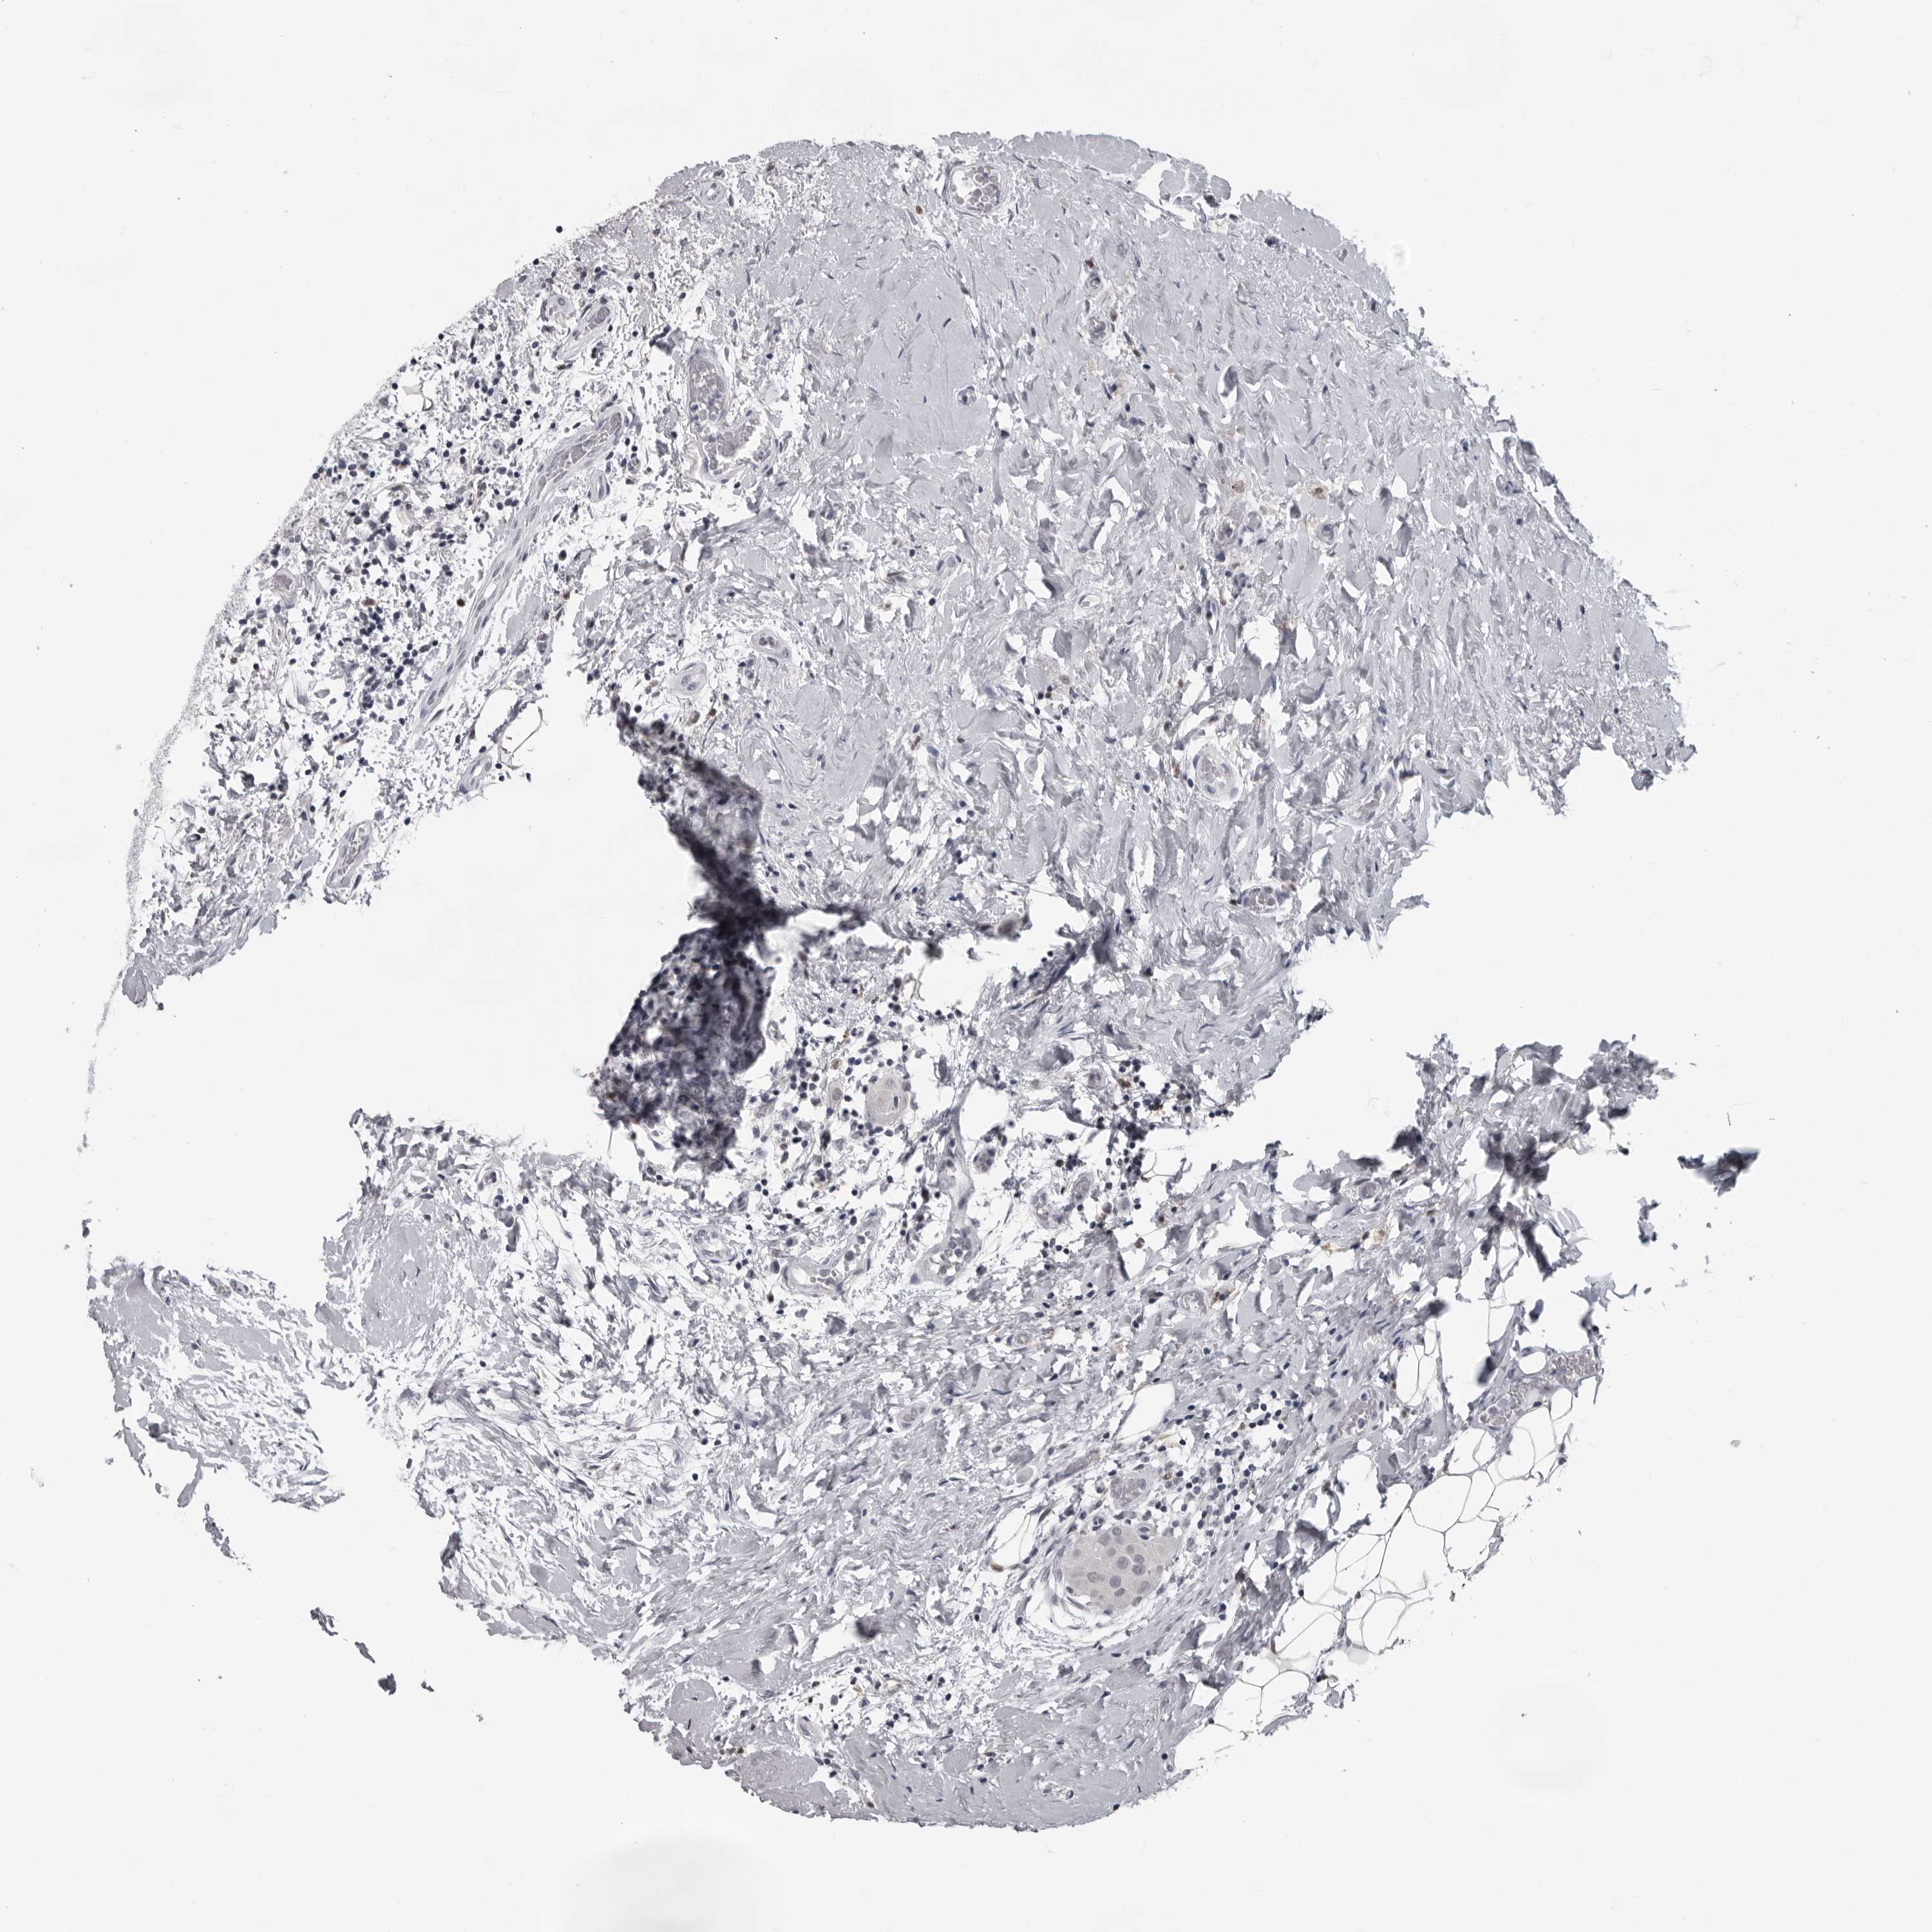

THYROID CANCER - Protein expressioni

A mouse-over function shows sample information and annotation data. Click on an image to view it in a full screen mode. Samples can be filtered based on level of antibody staining by selecting one or several of the following categories: high, medium, low and not detected. The assay and annotation is described here.

Note that samples used for immunohistochemistry by the Human Protein Atlas do not correspond to samples in the TCGA dataset.

Antibody stainingi

Antibody staining in the annotated cell types in the current human tissue is reported as not detected, low, medium, or high, based on conventional immunohistochemistry profiling in selected tissues. This score is based on the combination of the staining intensity and fraction of stained cells.

Each image is clickable and will lead to virtual microscopy that enables deeper exploration of all samples and also displays staining intensity scores, fraction scores and subcellular localization as well as patient and tissue information for each sample.

Antibody HPA028184

Staining

High

Medium

Low

Not detected

Intensity

Strong

Moderate

Weak

Negative

Quantity

>75%

75%-25%

<25%

None

Location

Nuclear

Cytoplasmic/membranous

Cytoplasmic/membranous,nuclear

Papillary adenocarcinoma, NOS

Follicular adenoma carcinoma, NOS